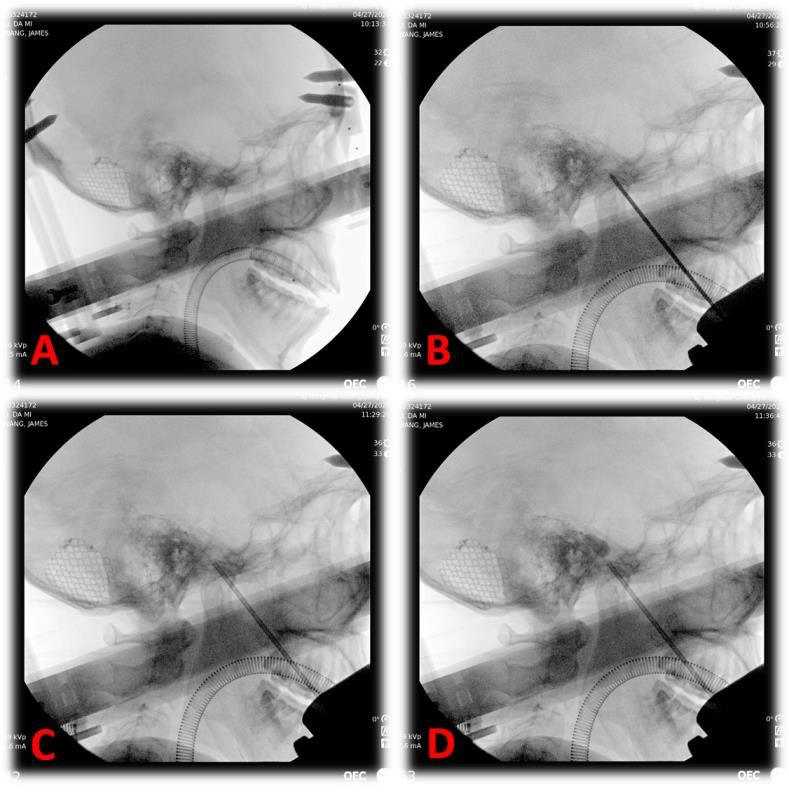

图为术中X光片提示穿刺位置准确

这种技术是用微创经皮穿刺的方法,在颅底一个叫迈克尔腔的地方打起一个花生米大小的小水球,机械压迫损毁三叉神经节和部分神经根以达到止痛目的。这种方法创伤小、安全可靠、恢复快、花费少。但手术需要精确定位,手术最大的挑战是要把穿刺针穿入10公分外的卵圆孔,大约有衬衫扣子1/4的大小。大多医院限于条件,都是在X线、C形臂、CT引导下徒手进行。

图为术中穿刺成功后球囊内注入造影剂

北京清华长庚医院运用机器人手术,其精度可达到亚毫米级,准确度更高,保证了一针入孔,实际术中仅用10秒钟即完成了穿刺操作,避免了重要血管、脑组织的损伤,而且减少了术中X线的照射,大大减少了患者的手术风险。同时,考虑到患者的美观和舒适,神经外科住院总医师董生将Leksell头架改装后连接手术机器人。这结合了立体定向技术和机器人技术,化繁为简,省略了患者需要剃发和在头上固定骨性标志点的操作。